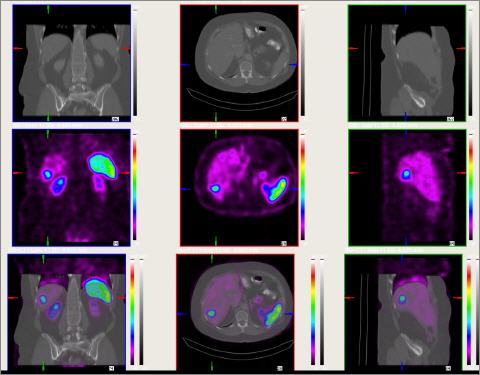

In diesem Beispiel sind Leberherde zu sehen.